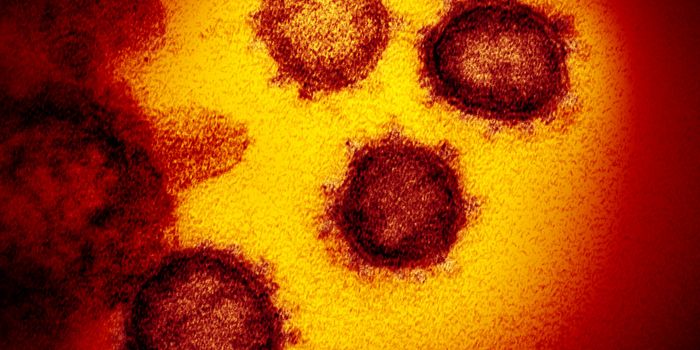

AUG 19, 2020Cell & Molecular BiologyAs the pandemic virus, SARS-CoV-2 continues to cause tens of thousands of new cases of COVID-19 every day in the United ...

FEB 08, 2020MicrobiologyIn China, authorities are still struggling to contain the new coronavirus that emerged in the city of Wuhan and has sinc ...

APR 27, 2020MicrobiologyThe pandemic virus that causes COVID-19 has now infected nearly 3 million people, and killed over 200,000.

MAY 10, 2021MicrobiologyThe pandemic virus SARS-CoV-2 has changed the world in devastating ways, taking hundreds of thousands of lives & new var ...

MAR 03, 2020MicrobiologyThere have now been nine deaths in the United States, all in Washington state from COVID-19, the illness caused by the n ...

MAR 10, 2020MicrobiologyThe vast majority (97.5%) of people will develop symptoms of infection within 11.5 days of exposure to the virus.

NOV 01, 2020MicrobiologySARS-CoV-2, which causes COVID-19 has to get into cells to cause infection. It does so with a spike protein on its surfa ...